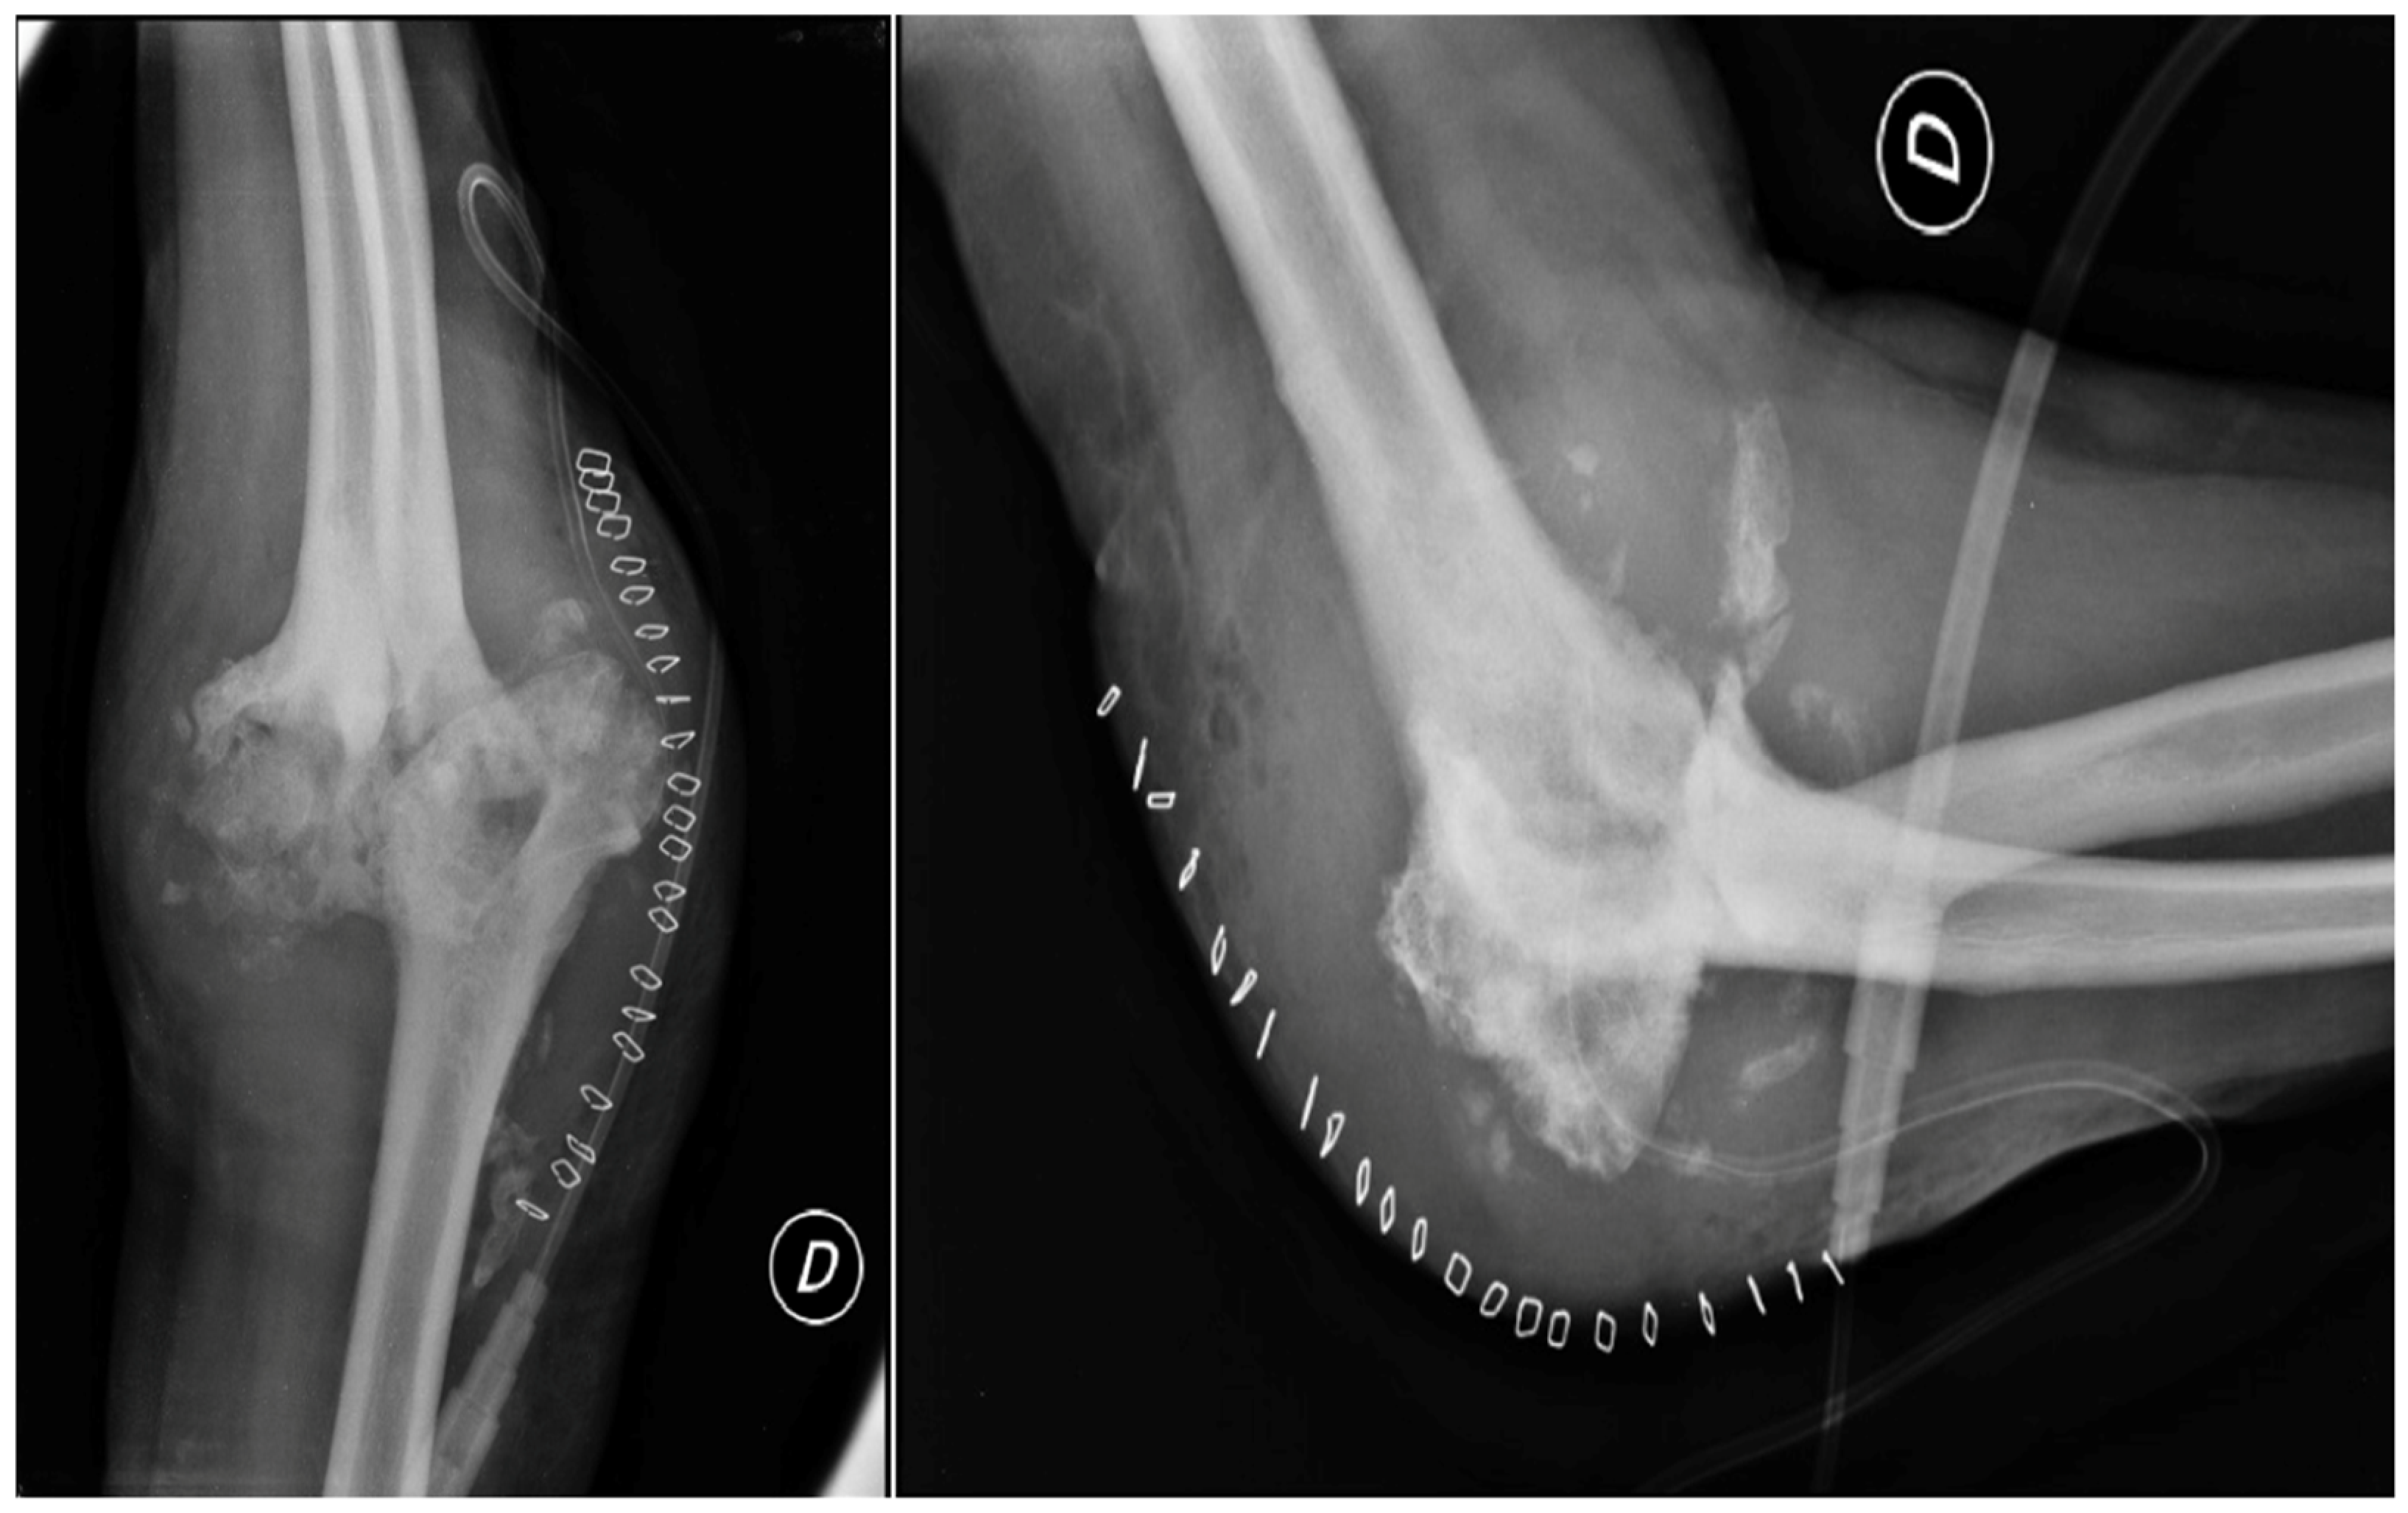

2. Case Presentation

2.3. Further Investigations

2.4.3. Open Debridement

- Evidence from the Scientific Literature